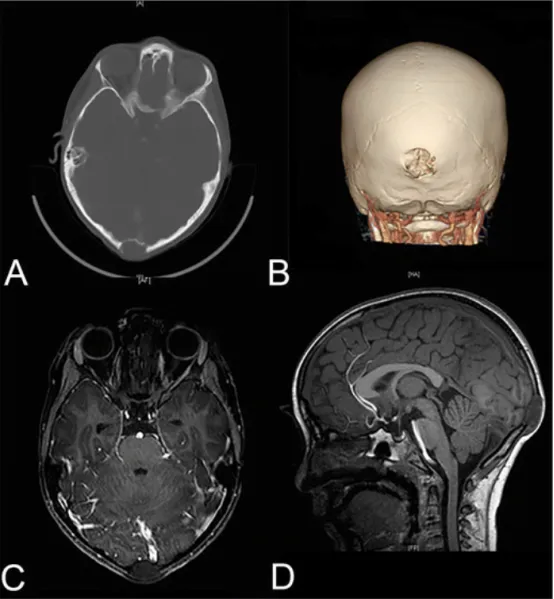

年幼的孩子是否健康,始终是牵挂在父母心头的一件大事。如果孩子的脑袋上莫名长了一个小肿块,会是什么原因呢?不小心摔倒?被重物砸到?其实,除了这些,还可能是一个更加可怕的真相...